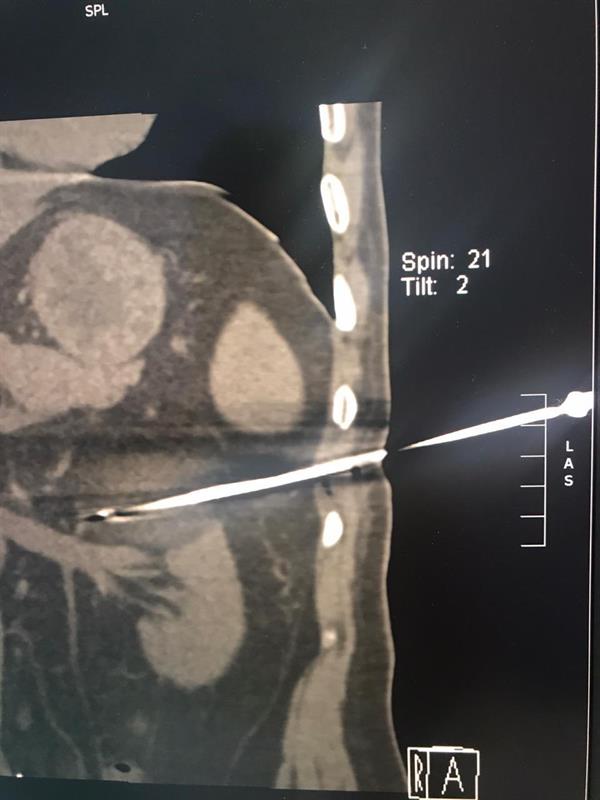

نجح فريق طبي بمدينة الملك عبدالله الطبية، من استئصال ورم سرطاني من الكلية اليسرى لمريض بالعقد السادس من العمر مع الحفاظ عليها وعلى وظيفتها بتقنية التبريد.

وأبانت مدينة الملك عبدالله الطبية، أن العملية تعد الأولى من نوعها على مستوى المنطقة الغربية، كما جرى تطبيق كافة الإجراءات الاحترازية الوقائية.